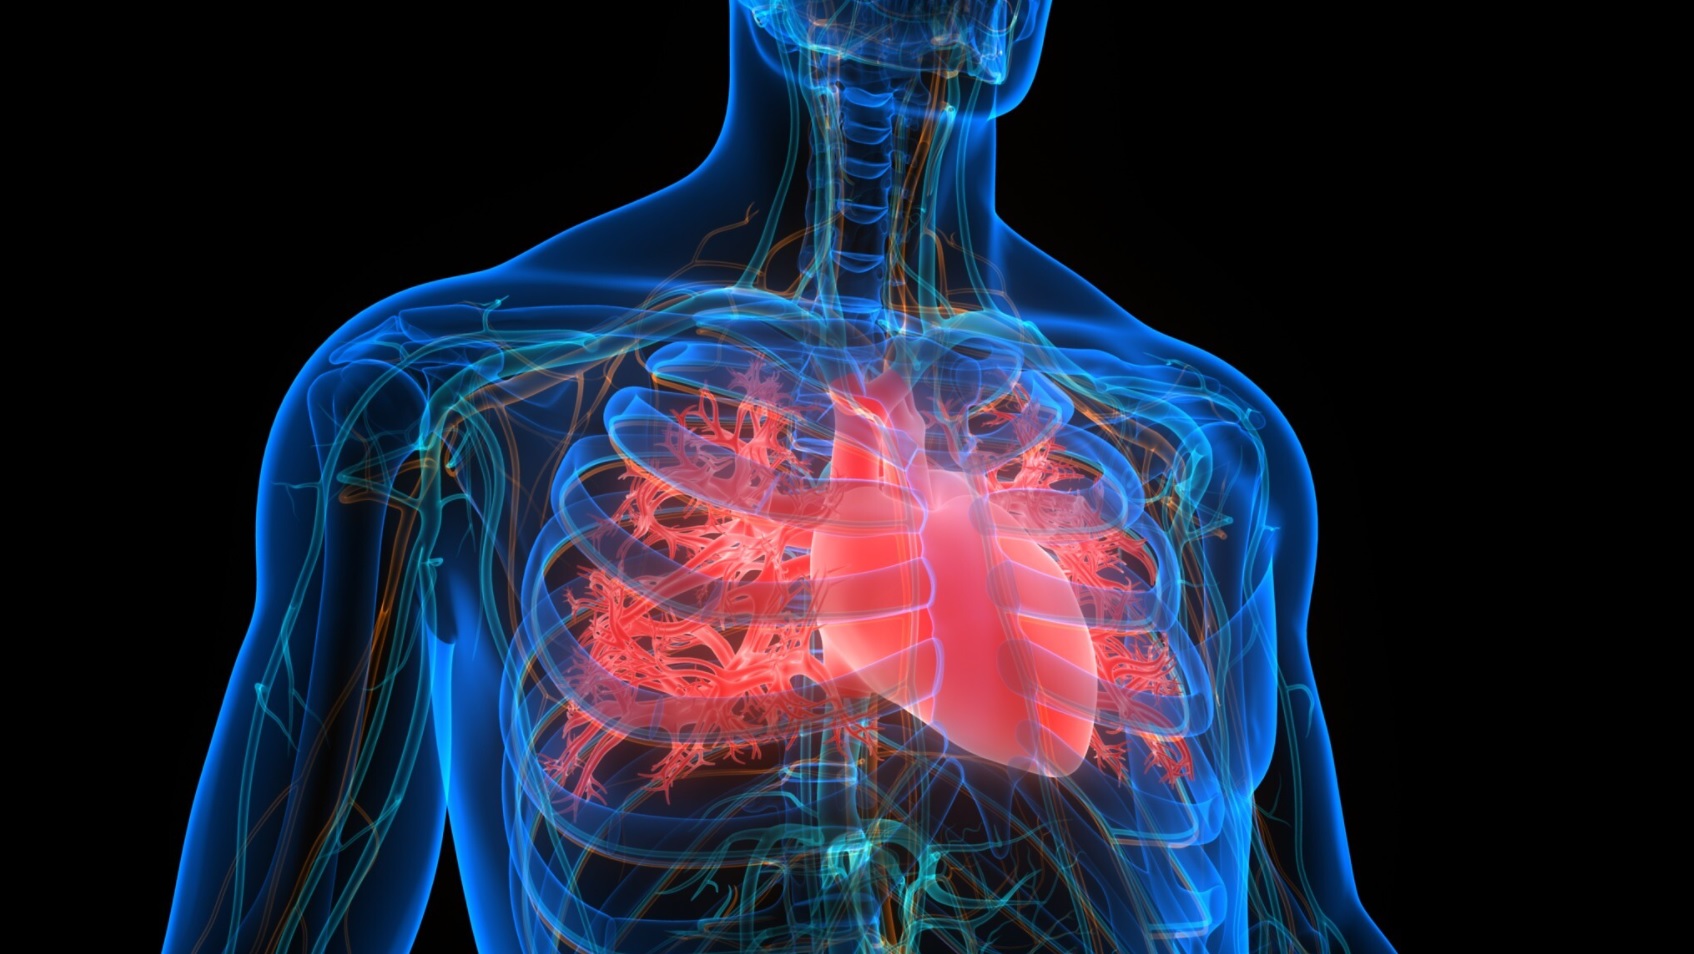

كشف مركز شيبا الطبي، أمس الأحد، تسجيل أول حالة معلن عنها في إسرائيل لالتهاب القلب المرتبط بالإصابة بمتحور أوميكرون من فيروس كورونا، بحسب تقرير لموقع "تايمز أوف إسرائيل"، الأمر الذي لم تعلق عليه منظمة الصحة العالمية حتى الآن.

وقال الأطباء في المركز، لقناة 12، إن رجلا يبلغ من العمر 43 عاما تم نقله إلى العناية الخاصة بفيروس كورونا، ويعالج حاليا من التهاب عضلة القلب.

وأعرب البروفيسور شلومي ماتيتسكي، خبير أمراض القلب في المستشفى، عن قلقه لكونها الحالة المرضية الأولى المشخصة بالتهاب القلب المرتبط بالمتحور.

وكانت المتحورات السابقة من الفيروس قد تسببت في التهاب عضلة القلب والتهاب التامور (التهاب البطانة المحيطة بالقلب).